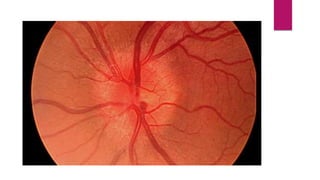

Normal fundus

DISC

Clear; the central area of the cup is pale.

RETINA

A normal red/orange color; the macula is dark.

VESSELS

Arteries appear bright red, vein slightly purple. Arterial to

venous ratio is about 2 to 3.